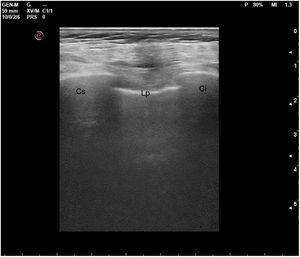

En el pulmón, la ecografía se comporta como un densitómetro. En un pulmón aireado (ya sea normal o con hiperaireación, como ocurre en el enfisema), la gran diferencia de impedancia acústica entre la pared torácica y el aire no permite obtener una imagen anatómica. En este caso, se evidencia la línea pleural, una franja horizontal hiperecogénica altamente reflectante del haz de ultrasonido. En el corte longitudinal (fig. 13), la línea pleural aparece entre 2 costillas sucesivas, en el denominado signo del murciélago: las corticales de las costillas, hiperecogénicas y con sombra posterior, constituirían las alas del murciélago, y la línea pleural, el cuerpo. En el corte oblicuo o intercostal (fig. 14), la línea pleural se presenta en su máxima extensión. Es una estructura dinámica, que se desliza con los movimientos respiratorios en el denominado deslizamiento (o «sliding») pleural. Al tratarse de una superficie altamente reflectante del ultrasonido, genera unos artefactos en profundidad, denominados líneas A. Las líneas A son hiperecogénicas, horizontales y paralelas, siempre a la misma distancia entre ellas (que es la misma distancia que hay entre la línea pleural y la sonda). Su presencia indica que la sonda está colocada perpendicular a la pleura, y no traduce enfermedad.